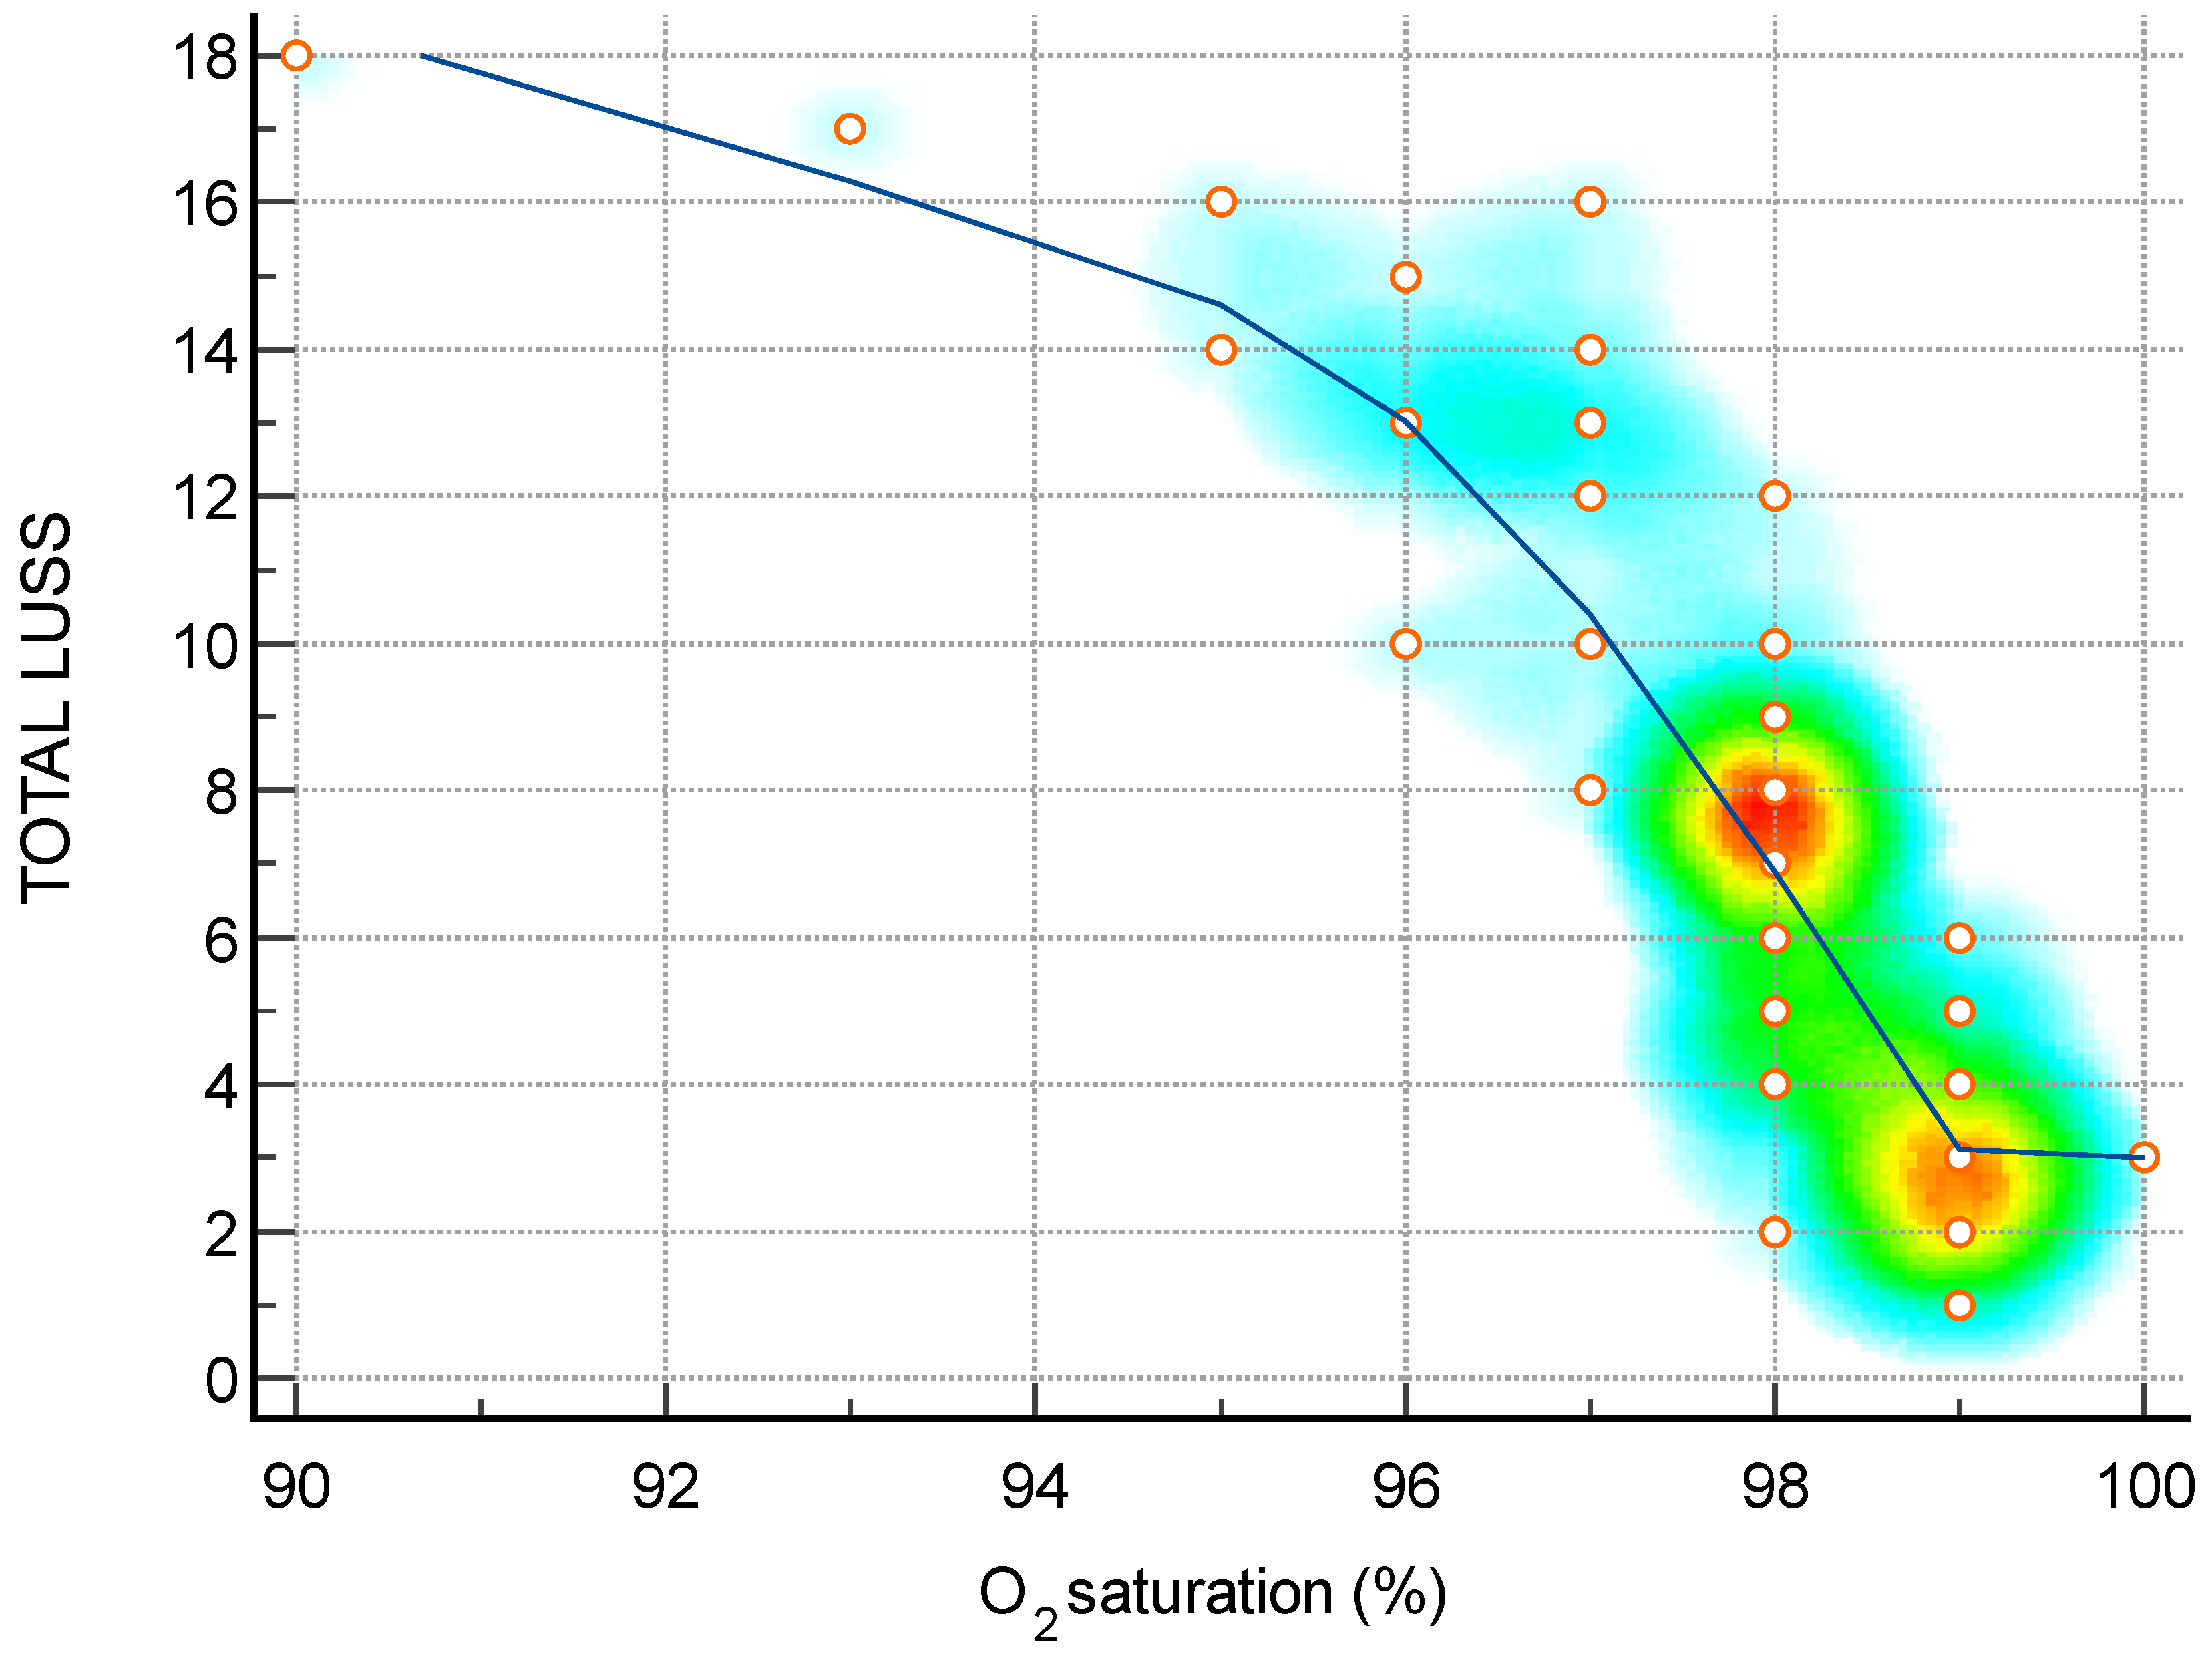

| O2 saturation (%)—Figure 6 | −0.88 | −0.93 to −0.79 | <0.0001 |